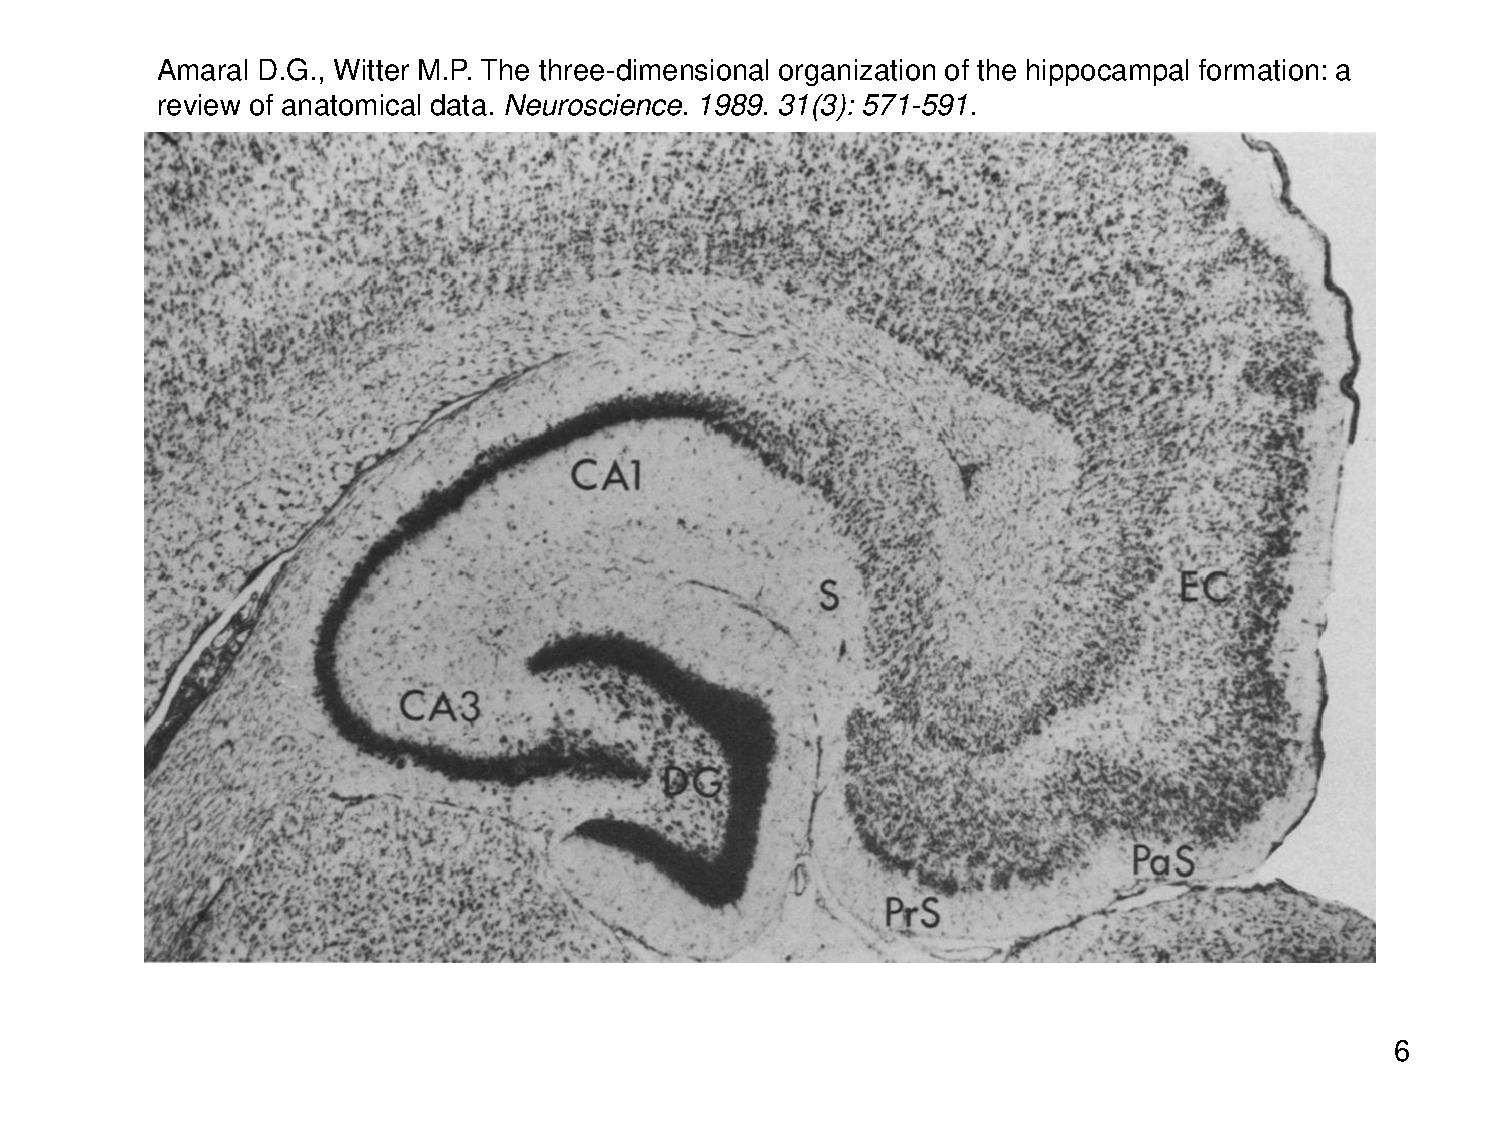

В 2014 году Нобелевскую премию по физиологии и медицине получили исследователи «навигационной системы» мозга.